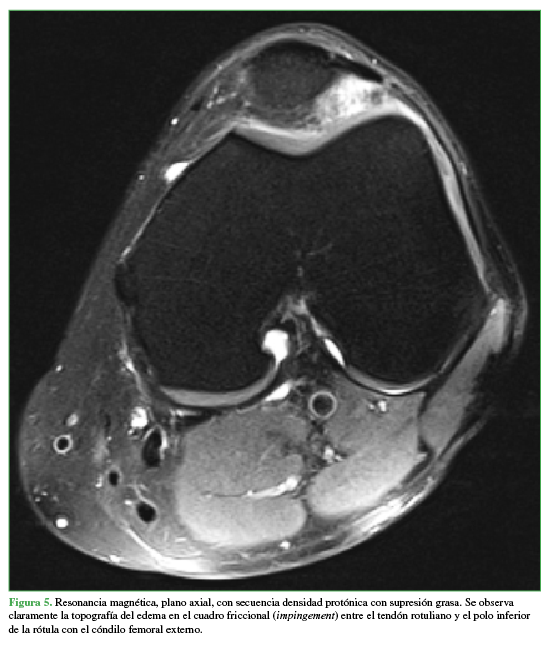

PropiaLuego se le realizó una resonancia magnética (RM) (Figuras 2,3,4,5,6) que mostró como hallazgo central la presencia de hiperintensidad en las secuencias líquido sensibles indicativa de edema en el sector superolateral del paquete adiposo infrarrotuliano (PAI) o de Hoffa. Se constató un desgarro degenerativo en el menisco externo y pequeños quistes parameniscales asociados, así como condromalacia rotuliana de bajo grado (imágenes no mostradas). Las estructuras óseas y ligamentarias eran de características normales.

Se observa claramente la topografía del edema en el cuadro friccional (inpingement) entre el tendon rotuliano y el polo inferior de la rótula con el cóndilo femoral externo.

Propia

El edema se localiza por debajo del borde inferolateral de la rótula y es fácilmente accesible a la exploración física generando dolor a la palpación.